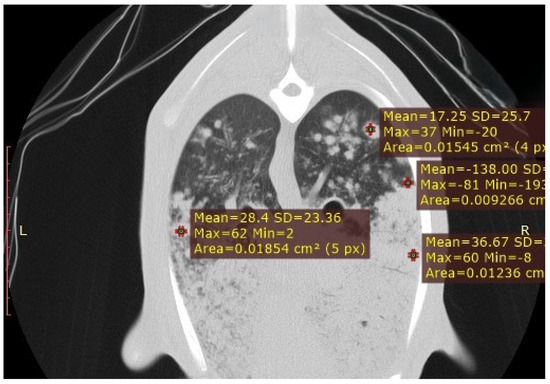

Use of Computed Tomography in the Clinical Diagnosis of Lower Respiratory Tract Diseases in Sheep

Lower airway diseases are a major health concern in sheep, often presenting with overlapping clinical signs that hinder accurate diagnosis. This study evaluated the diagnostic value of computed tomography (CT) in 58 adult sheep examined in northeastern Spain between 2017 and 2024. All [...] Read more.

Lower airway diseases are a major health concern in sheep, often presenting with overlapping clinical signs that hinder accurate diagnosis. This study evaluated the diagnostic value of computed tomography (CT) in 58 adult sheep examined in northeastern Spain between 2017 and 2024. All animals underwent full clinical examination, CT under general anaesthesia, and post-mortem investigation. CT identified 82 pulmonary lesions, including interstitial pneumonia, respiratory complex, gangrenous pneumonia, caseous lymphadenitis, parasitic pneumonia, pulmonary adenocarcinoma, and pulmonary hydatidosis. Tissue density measurements provided additional information regarding disease stage and severity. The level of agreement between CT findings and definitive diagnoses consistently exceeded that of clinical evaluation, reaching almost perfect concordance for several conditions. Moreover, CT revealed concomitant respiratory pathologies within the same animal, many of which were not detected by conventional diagnostic methods. Although thorough individual clinical examination remains essential for the correct interpretation of imaging findings and the accurate diagnosis of respiratory disorders in the field, these results demonstrate that CT provides superior diagnostic accuracy compared with standard approaches and yields valuable insights for both clinical practice and research. Despite its practical limitations, CT could represent a major advance in improving health, welfare, and productivity in sheep farming. Full article